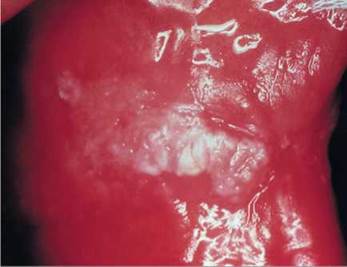

Pseudomembranous candidiasis

Pseudomembranous candidiasis, classically termed 'thrush' (Fig. 35.2), is an acute infection but may persist intermittently for many months or even years in patients using corticosteroids topically or by aerosol, in HIV-infected individuals, and in other immunocompromised patients. It may also be seen in neonates and in the terminally ill, particularly in association with serious underlying conditions such as leukaemia.

Characterized by white membranes on the surface of the oral mucosa, tongue and elsewhere. The lesions develop to form confluent plaques that resemble milk curds and can be wiped off to reveal a raw, erythematous and sometimes bleeding base. Hence, some consider pseudomembranous and the erythematous variants a continuum and a single entity (i.e., two stages of the same disease).

Fig. 35.2 Pseudomembranous candidiasis (thrush) of the palate in a human immunodeficiency virus (HIV)-infected individual.